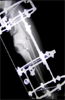

Post

Op

Hinged construnct for oblique plane deformity with osteotomy above malunion